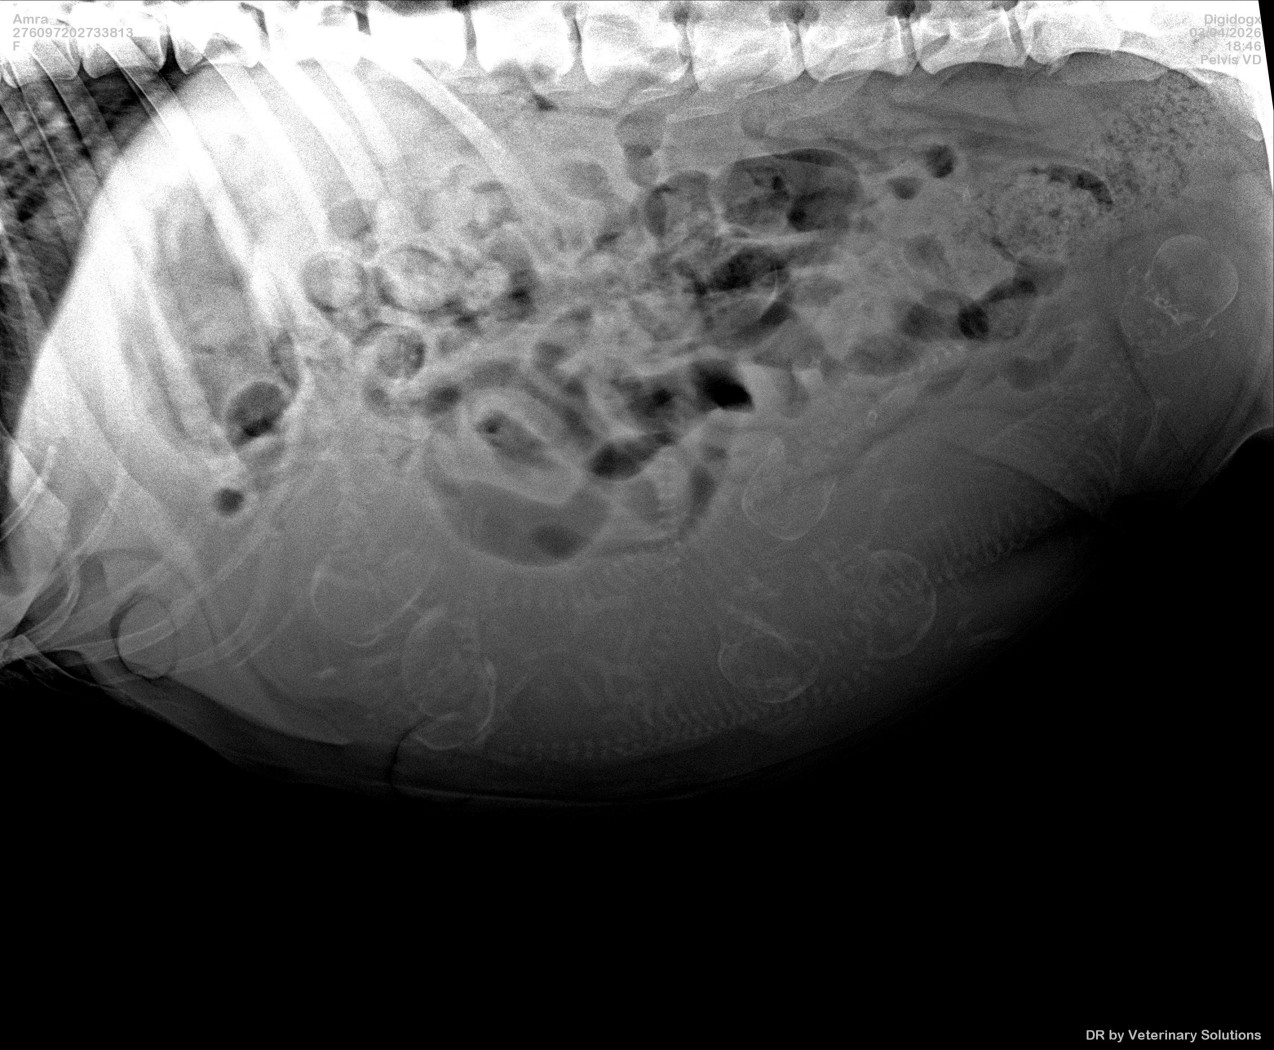

Amra nu 7,5 week drachtig en geniet nog volop van de rust.